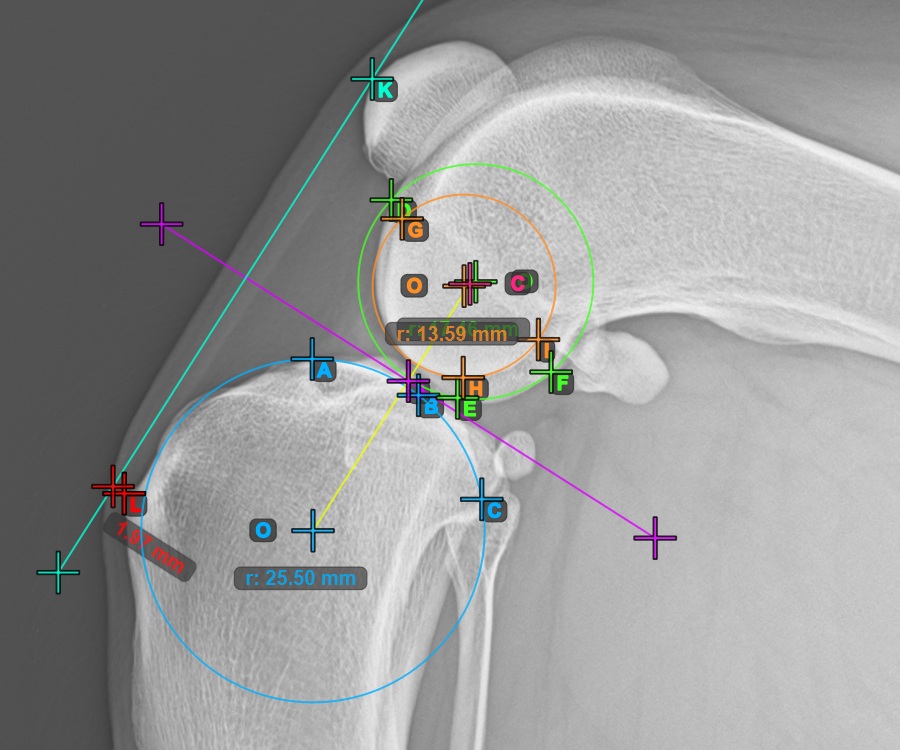

Continue by marking the three points on the articular surface of the first Condylus Femoris.

Mark the three points on the main condylus of the femoral bone (Condylus Femoris). Regardless of the order, make sure to mark the most cranial point, the most caudal point and the midpoint of the Condylus Femoris. A circle will be automatically constructed based on the three placed points.

The image below represents a typical placement of the three points on the first Condylus Femoris.